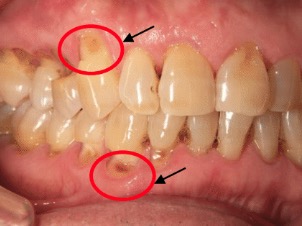

①歯周病による歯根露出

歯周病で歯槽骨が吸収されていくと歯肉が後退する(歯茎が下がる)ように歯根の象牙質が露出する事で終わります。